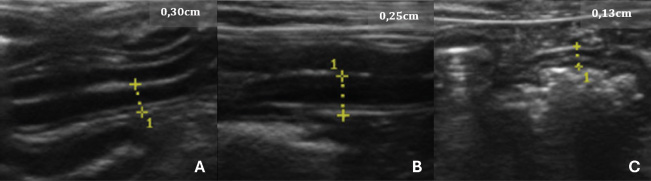

When assessing the thickness of the wall of the GIT layers, it was possible to see thickening in centimeters in association with those individuals in G2 who showed thickening in more than one gastrointestinal segment (Fig. 2) or in isolation, in which only one component of the structures analyzed was altered in the USG measurements. In G2, 100% (n=15/15) of the dogs had one or more parts of the GIT thickening. The G2 dogs showed higher values in the intestinal wall USG measurement compared to G1. The differences in the values for the duodenum, jejunum, ileum, and colon were significant in the mean comparison tests (p < 0.05) (Fig. 3). The variables obtained in the G2 group were analyzed using Pearson’s correlation test, which correlated the thickness of different intestinal segments with laboratory variables. This was done with the keratometric parameters, leukometry data, TPPs, and serum biochemistry.

Fig. 2. USG images of the intestines of G2 dogs (asymptomatic with intestinal thickening). A, duodenum; B, jejunum; C, descending colon. The yellow dashed lines between the crosses indicate the measurements, and the values are shown in the top right-hand corner of each image.